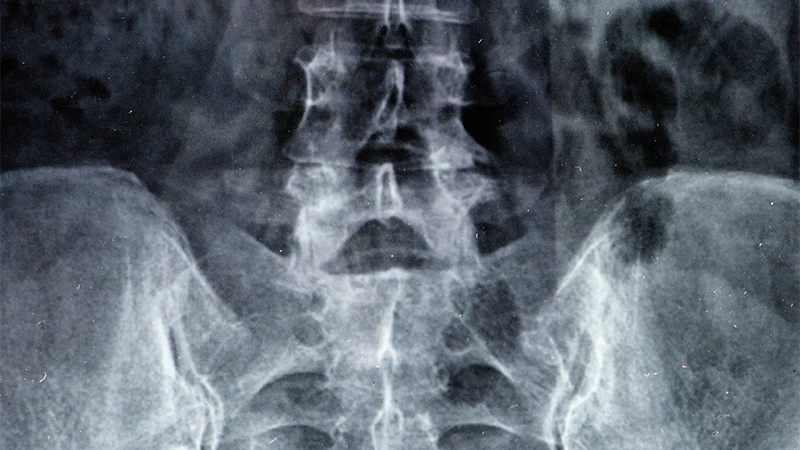

Doktorlar, kalça kireçlenmesini değerlendirirken hastanın anamnezini alır, fizik muayene gerçekleştirir ve ağrının derecesini ve eklem hareketliliğini incelerler. Kesin tanı koymak için genellikle röntgen, MRI veya CT gibi görüntüleme yöntemleri kullanılmaktadır. Bu görüntüleme teknikleri, eklemdeki kireçlenme derecesini, kıkırdak hasarını ve eklemde oluşan osteofitleri ortaya çıkarır.